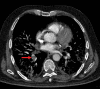

Chest CT has a potential role in the diagnosis, detection of complications, and prognostication of coronavirus disease 2019 (COVID-19). Implementation of appropriate precautionary safety measures, chest CT protocol optimization, and a standardized reporting system based on the pulmonary findings in this disease will enhance the clinical utility of chest CT. However, chest CT examinations may lead to both false-negative and false-positive results. Furthermore, the added value of chest CT in diagnostic decision making is dependent on several dynamic variables, most notably available resources (real-time reverse transcription-polymerase chain reaction [RT-PCR] tests, personal protective equipment, CT scanners, hospital and radiology personnel availability, and isolation room capacity) and the prevalence of both COVID-19 and other diseases with overlapping manifestations at chest CT. Chest CT is valuable to detect both alternative diagnoses and complications of COVID-19 (acute respiratory distress syndrome, pulmonary embolism, and heart failure), while its role for prognostication requires further investigation. The authors describe imaging and managing care of patients with COVID-19, with topics including (a) chest CT protocol, (b) chest CT findings of COVID-19 and its complications, (c) the diagnostic accuracy of chest CT and its role in diagnostic decision making and prognostication, and (d) reporting and communicating chest CT findings. The authors also review other specific topics, including the pathophysiology and clinical manifestations of COVID-19, the World Health Organization case definition, the value of performing RT-PCR tests, and the radiology department and personnel impact related to performing chest CT in COVID-19. ©RSNA, 2020.